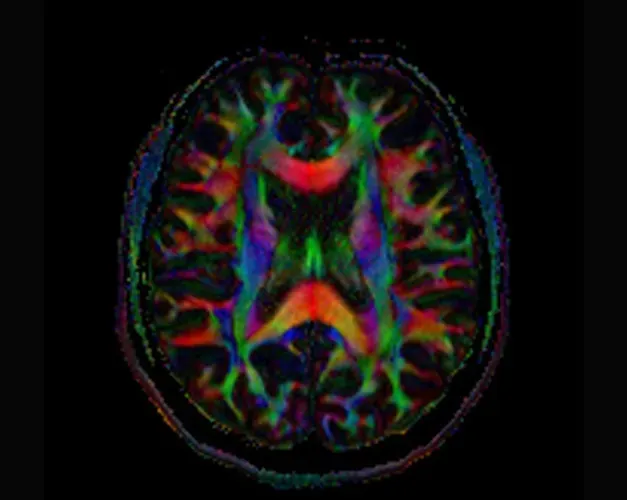

Colourful scan of a human brain with Alzheimer's